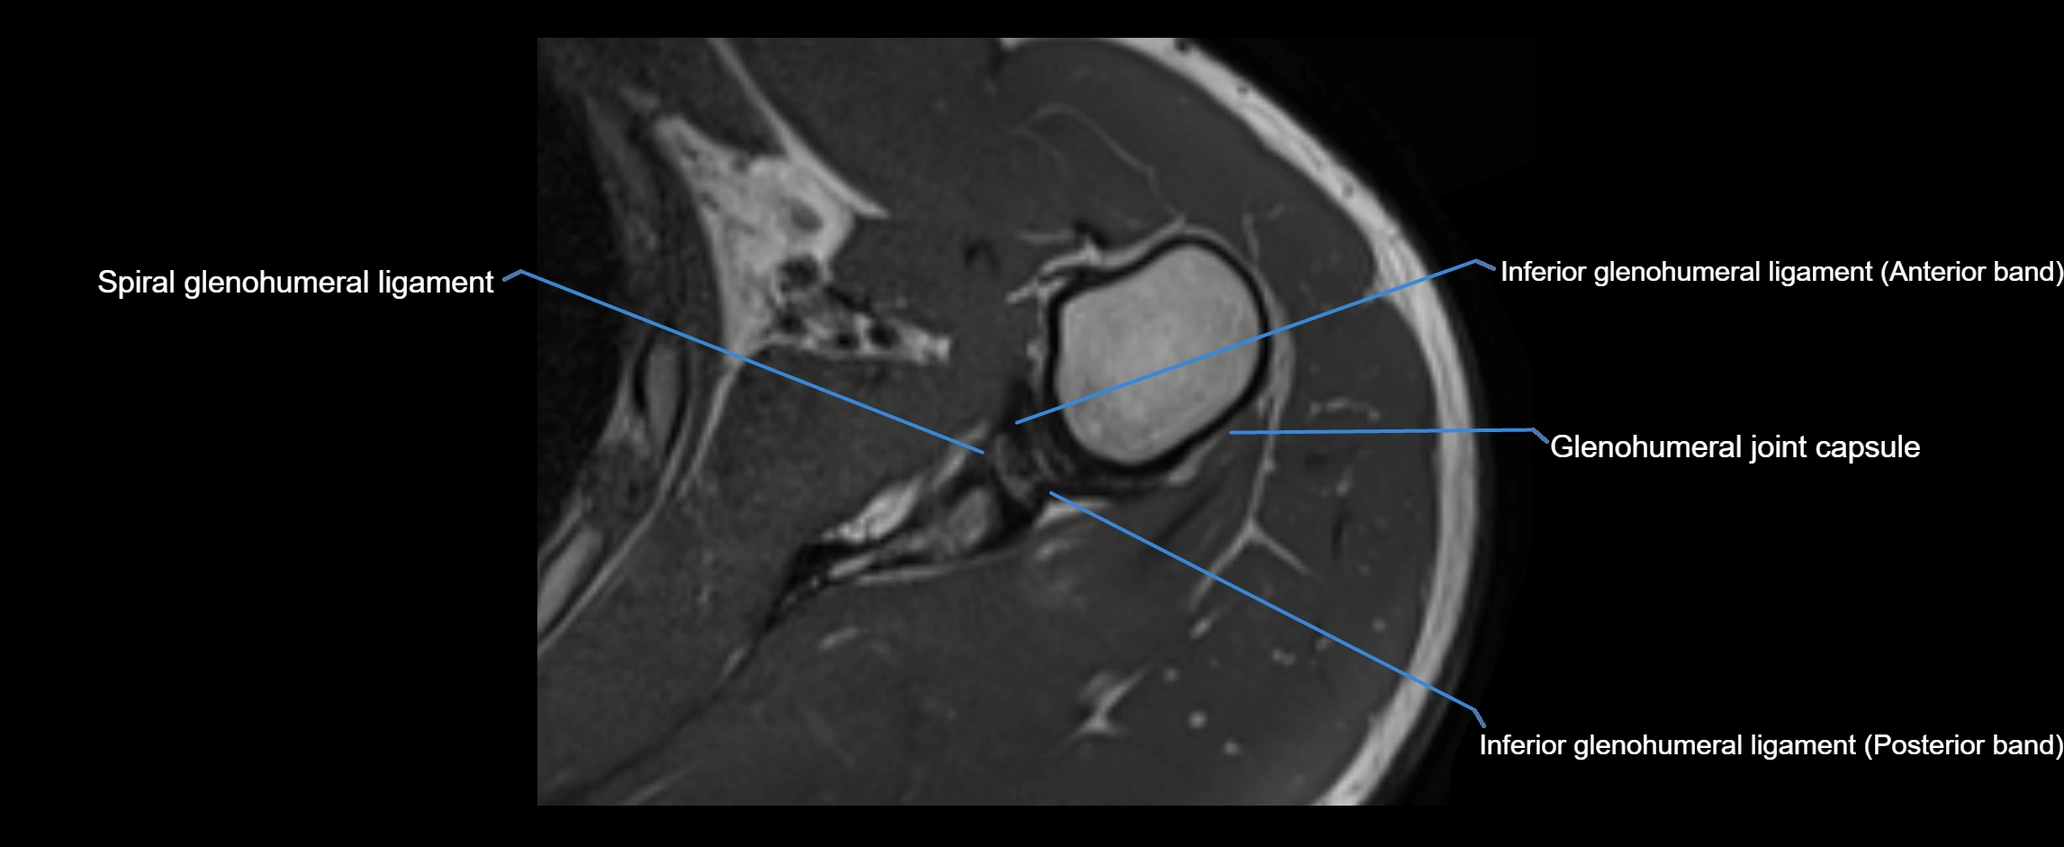

MRI Appearance

• T2-weighted images:

• STIR:

• Proton Density Fat-Saturated (PD FS):